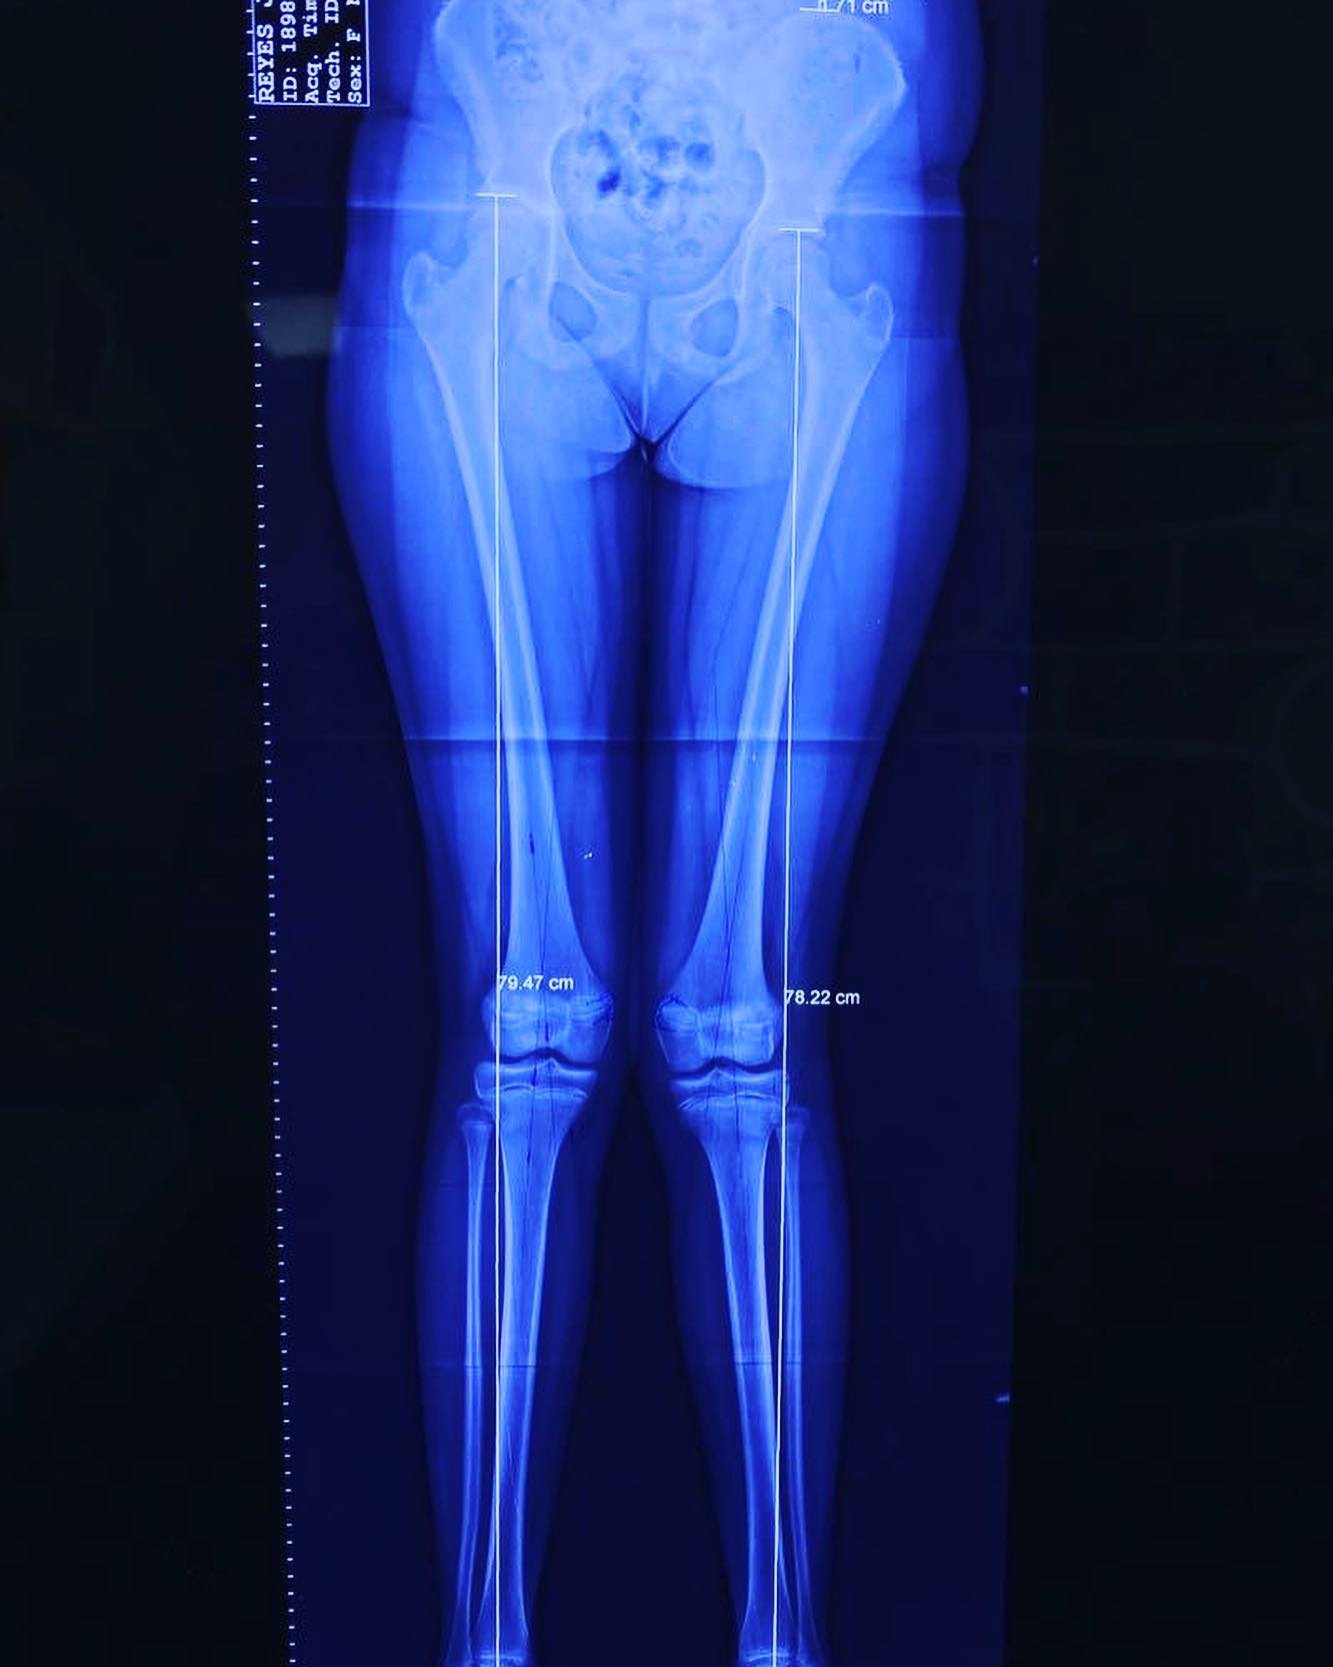

• Discrepancias de longitud en miembros pélvicos

Consulta y desarrolo de nuestros pacientes despues de ser intervenidos, lo que muestra la evolucion y avances desde la primera vez que nos visitaron